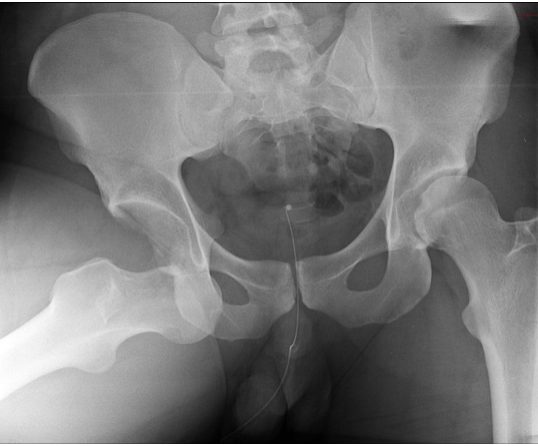

Чтобы получить исчерпывающие сведения о состоянии пациента, ему делают обзорную рентгенограмму таза в прямой проекции. Проведение рентгенографии только одного сустава является ошибкой. Для полноценного анализа рентгенологу необходимо видеть снимки обоих ТБС. Часто выявить патологию ему помогает именно сравнение.

- Проведение исследования. Для получение обзорной рентгенограммы пациента укладывают на спину. Таз исследуемого не должен наклоняться и поворачиваться. Чтобы получить правильное отображение шеечно-диафизарного угла, рентгенолог разворачивает обе стопы больного кнутри на 15 градусов. Установив рентгеновскую трубку, он выходит из комнаты и делает снимок.

Помимо обзорного снимка, пациенту также делают рентгенографию больного сустава в боковой проекции. Существует несколько методик его получения. Выбор какой-либо из них зависит от того, какие структуры сустава требуется визуализировать. Исследование может проводиться как стоя, так и в лежачем положении.